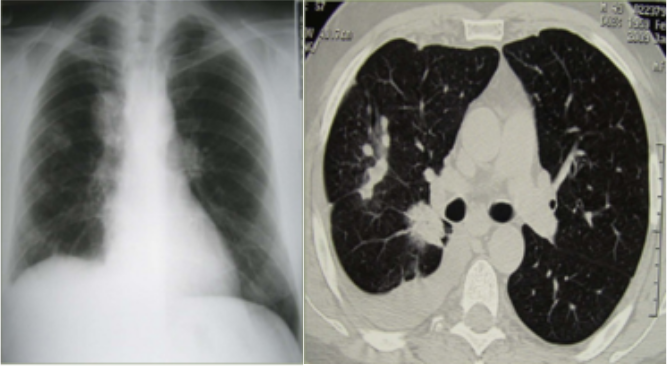

Mellkasröntgen felvétel:

• a jobb tüdőben centrálisan 5 x 3 cm-es elmosódott szélű, inhomogén karéjozott árnyéktöbblet, emellett a jobb tüdőben a középső tüdőmezőben egy 2,5 x 3 cm-es lobulált inhomogén árnyék volt látható.

A CT felvétel a centrális terime mellett a bifurkációs carina alatt kórosan megnagyobbodott nyirokcsomót mutatott, a jobb tüdőben többgócból álló infiltrátum volt igazolható. A bronchoszkópos mintavétel patológiai eredménye adenocarcinoma volt.